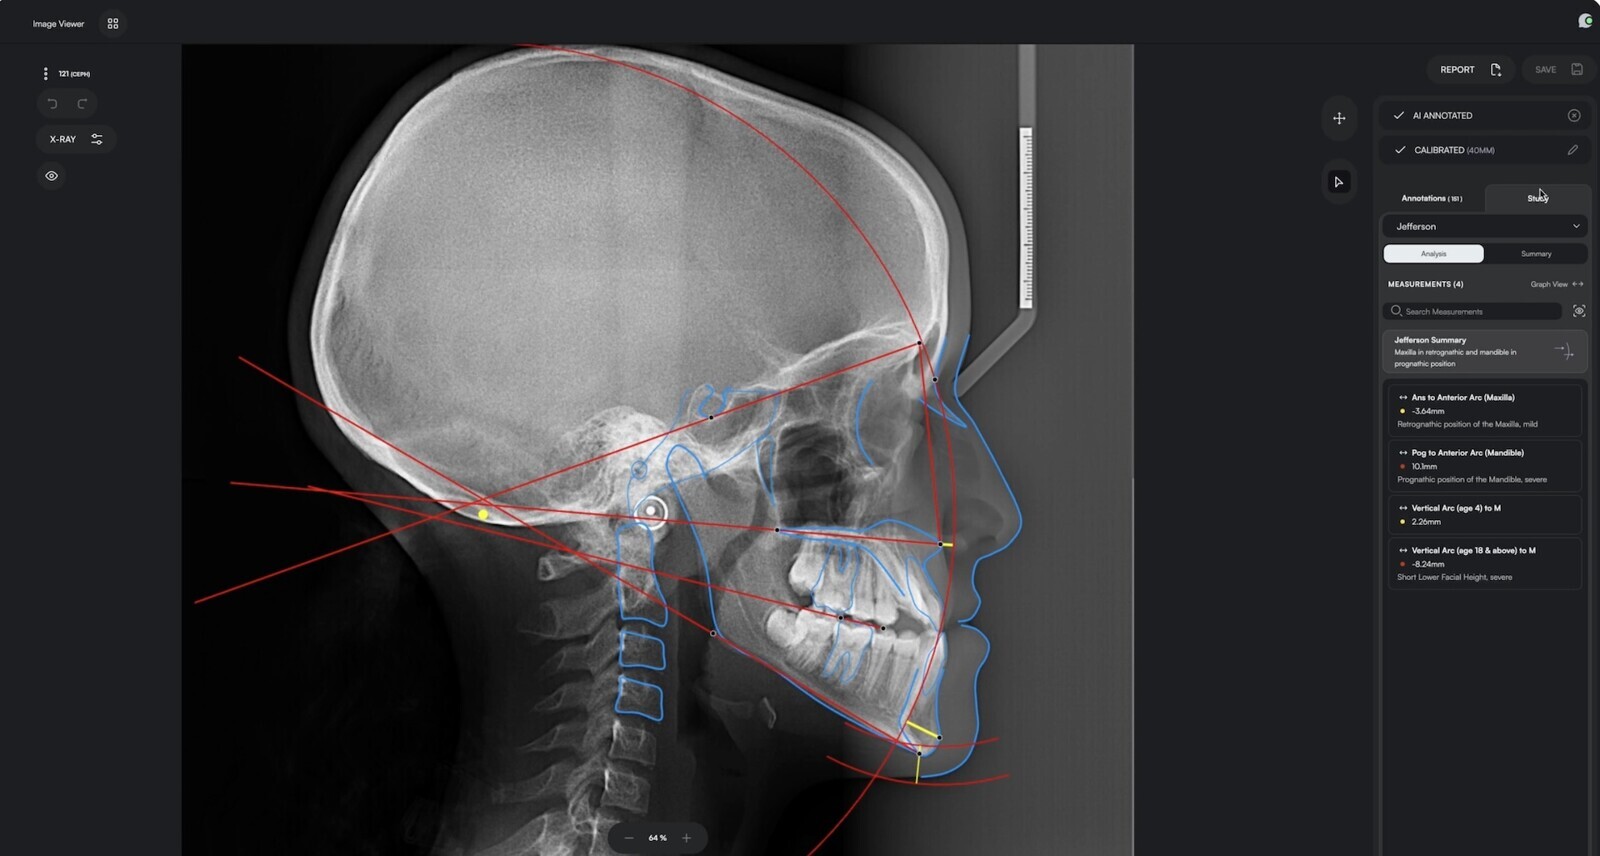

La tecnología de segmentación avanzada de Eyes of AI aporta una claridad visual, una precisión diagnóstica y una eficiencia de flujo de trabajo sin precedentes a las imágenes, lo que permite la generación de líneas de arcada, el trazado automático de nervios, la alineación volumétrica 3D y la segmentación dental.

Además, esta tecnología es compatible con los productos del Grupo W&H para proporcionar visualización en tiempo real del conducto mandibular, así como una capacidad pionera a nivel mundial para mostrar estructuras anatómicas críticas y generar mapas 3D de alta resolución de las cámaras pulpares y los sistemas de conductos radiculares.

Este nuevo sistema, que combina la plataforma de Eyes of AI y la gama de tomógrafos Seethrough de W&H, puede detectar características dentales invisibles mediante tecnología avanzada impulsada por inteligencia artificial. Foto: Eyes of AI

El modelado espacial avanzado ayuda a los odontólogos a colocar implantes, realizar tratamientos de conducto y extraer dientes impactados con precisión, a la vez que mejora la interacción con el paciente mediante visualizaciones 3D interactivas, lo que transforma las consultas y permite a los odontólogos mostrar procedimientos, opciones de tratamiento y resultados esperados. Además, Seethrough ofrece una integración perfecta con cualquier sistema de gestión clínica.